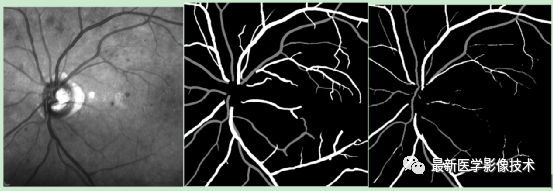

5、测试集部分分割结果